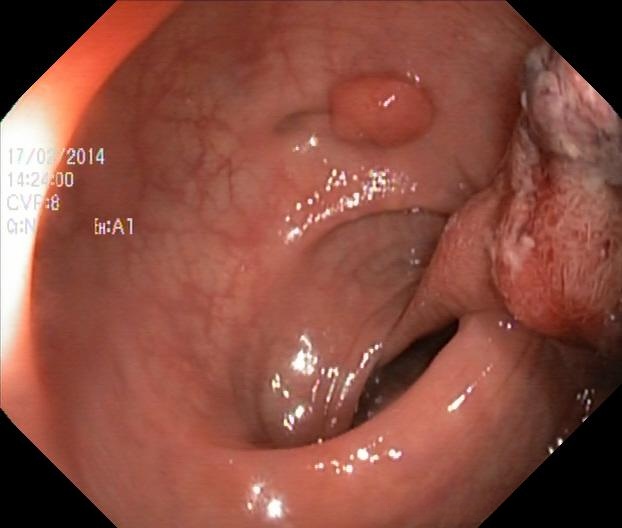

4、Kvasir : 该医学影像数据集是由挪威癌症登记处与挪威放射学协会共同发起开发的。该数据集包含了大量CT扫描图像资料,并旨在促进对肺结节及结肠息肉的自动检测与分割研究。

处理好后的COCO格式的数据集图像的总数为1000张,类型标签为病灶区域。